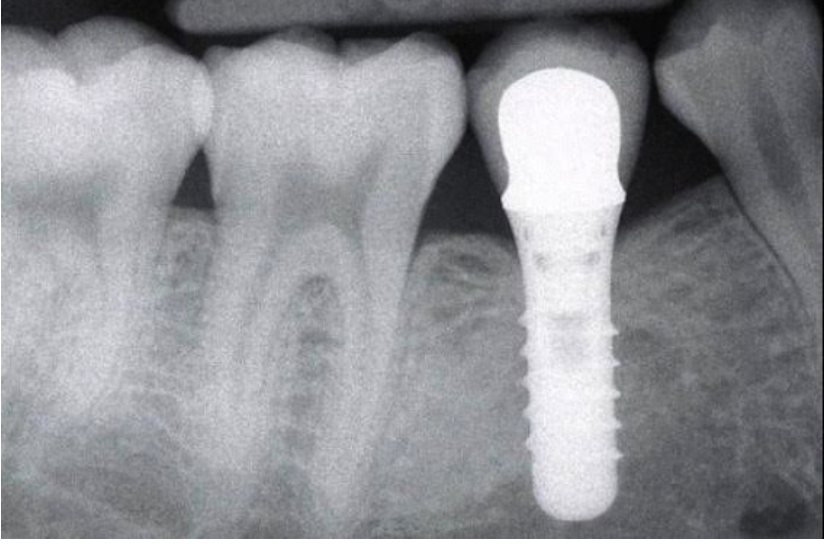

Исследование на рентгене после имплантации зубов

Раздел: Снимки-откровения